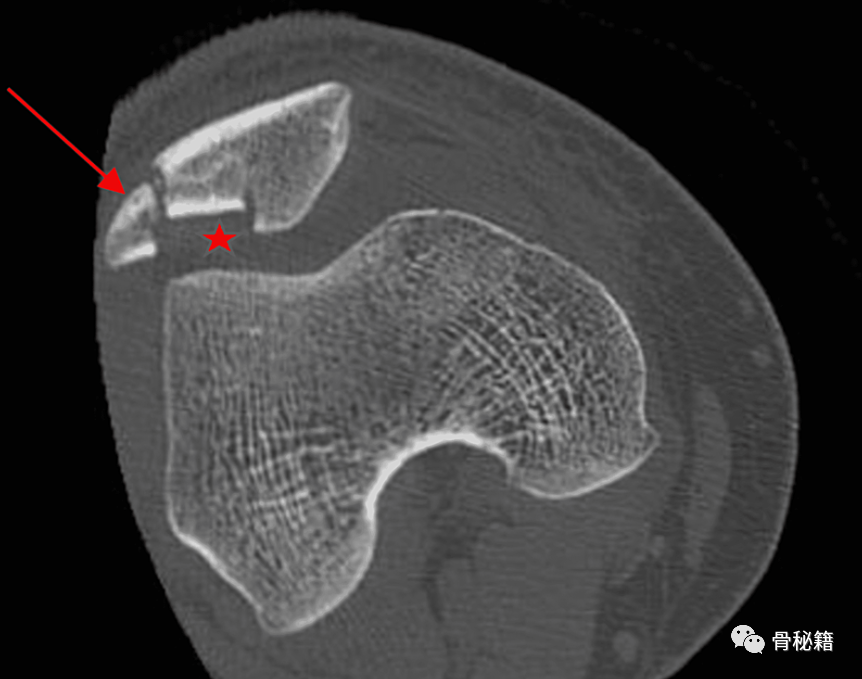

他的右膝前后位 (AP) X 线片显示髌骨外侧缘有垂直型骨折。

他的右膝CT扫描显示右髌骨粉碎性骨折,髌骨关节面凹陷